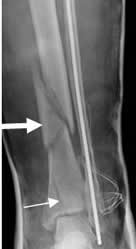

Fig 39. Fractura en mariposa.

Rx AP. Fractura conminuta en la tibia distal. En la parte superior tiene el aspecto en mariposa (Flecha gruesa) y en la inferior hay otra fractura vertical. El paciente tiene material de osteosíntesis en al peroné, por fractura previa.